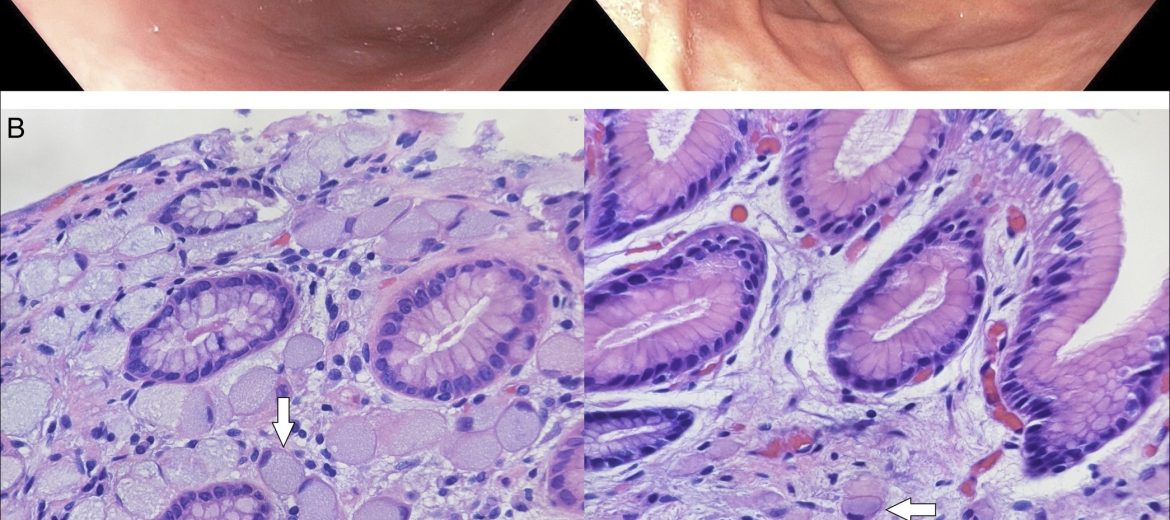

Гастроскопията установява слабо изразено възпаление на стомаха и нормално изглеждащи гънки, без язви или полипи. Взети са няколко биопсии, като в една от тях неочаквано се откриват ракови клетки с вид на ниско диференциран карцином тип „пръстен с камък“ (виж снимки отдолу в коментар). Злокачествените клетки са отрицателни за HER2 свръхекспресия. Изследването за бактерията Helicobacter pylori е отрицателно.

Компютърната томография показва нормален вид на коремните органи, без уголемени лимфни възли и с нормална дебелина на стомашната стена. Позитрон емисионната томография (ПЕТ) открива повишено натрупване на маркирана глюкоза в стомаха, но без метастази. Проведена е лапароскопска операция за отстраняване на стомаха. Хистологичното изследване на изрязания орган открива 156 зони на туморни клетки тип „пръстен с камък“ в ламина проприя. Резекционните линии са чисти, а в отстранените лимфни възли няма ракови клетки.

Наследственият дифузен стомашен рак е фамилна форма на ниско диференциран карцином по типа „пръстен с камък“. Причинява се от мутация в CDH1/E-cadherin гена. Мутацията се унаследява по автозомно доминантен път. Откриването на тумора в ранните стадии е изключително трудно, защото се развива и разпространява в подлигавичния слой и гастроскопията може да изглежда нормална. Носителите на мутацията имат и повишен риск от лобуларен карцином на гърдата.